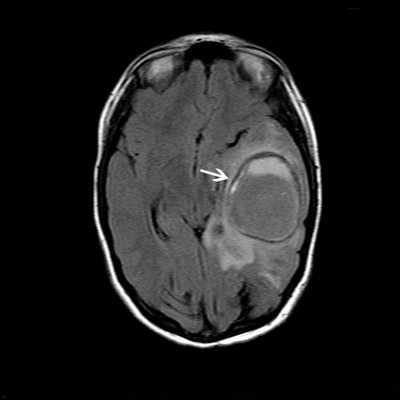

Магнитно-резонансная томография (МРТ) головного мозга проводится при подозрении на внутричерепные осложнения при воспалении среднего уха (отите).

МРТ головного мозга. Резко ограниченная овальная масса левой височной и теменной доли (отогенный абсцесс головного мозга, белая стрелка) после недавней операции на левом среднем ухе.